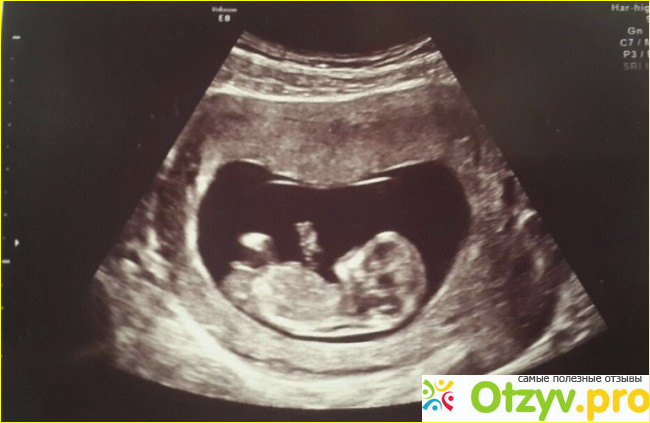

скрининг...???))) Добрый день!)))Наверное много кто знает, а может и наоборот не знают, что такое скрининг, особенно беременные девушки, которые, конечно же проходят эту процедуру)) Ведь это обследование в медицине, которое помогает выявить и...

Лучшее средство от перхоти - гильотина! Так кратко характеризуются скрининги. Суть такова, что на раннем этапе беременности выявляют "рисковых" детей. А дальше, после еще нескольких анализов, если таки пороки развития подтверждаются - выход только один. Потому как не научились еще лечить...